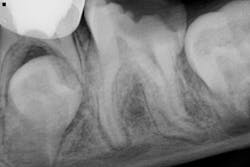

A 10-year-old male presents to have endodontic treatment on no. 19. He is asymptomatic currently, but he has a recent history of pain and slight swelling. Antibiotics were employed, and he is better now.

As can be seen radiographically, the tooth is fully matured apically. No. 18 is clearly present as is no. 20.

Personally, I’m leaning toward removal because no. 18 will soon erupt. Since we are at the point where no. 18 and no. 20 will be emerging in a close time frame, they will likely be in very close proximity. Furthermore, the patient will most likely need orthodontic intervention since he has moderate crowding from the bicuspids to incisors.

My thought process is this: If we can have no. 18 erupt, as it appears to be "tilting,” then orthodontics can be employed to "tuck" it into the no. 19 position. Then we will have a new first molar, so to speak, in its position as opposed to having to do traditional endo and crown placement.